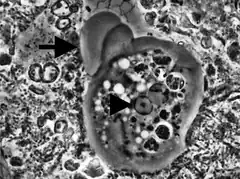

L'activité principale de l'amibe Entamoeba gingivalis dans les crevasses parodontales infectées, en plus de se déplacer, consiste à se nourrir des noyaux des globules blancs polymorphonucléaires neutrophiles. À la suite de l'adhésion du PMN et à son engourdissement, l'amibe pénètre le cytoplasme pour atteindre le noyau et littéralement succionner son contenu via la pression négative du pseudopode. Sa nourriture ainsi ingurgitée est digérée progressivement à l'intérieur de l'endoplasme. La phagocytose peut parfois se poursuivre pour plus de 20 noyaux ingurgités. Cette activité laisse en place un PMN énucléé, incapable d'accomplir son apoptose préprogrammée et probablement son activité NETS, qui sera déversé sur les tissus environnants entrainant des enzymes protéolytiques à partir des restes de cette cellule fantôme dès lors hors contrôle et capable alors de destruction cellulaire.